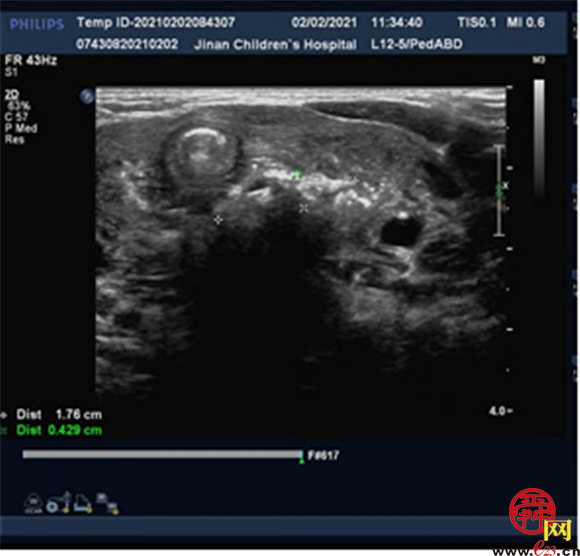

结合患儿病史,李华副主任医师做出快速诊断,考虑异物嵌顿食管可能,立即办理住院并联系相关科室,完善食管彩超及颈胸部CT了解异物位置、周围粘膜情况、是否存在并发症,为行电子胃镜下异物取出术做好充分准备。

颈部及胸部CT:C6/7水平脊柱前方见条状中空高密度影,大小约19.6*5.0*6.9mm,周围软组织肿胀,向上延伸至咽后间隙,向下至上纵隔区,组织间隙显示模糊,可见散在多发点、片状气体密度影,以高密度影周围为著,相应区域气管受压前移,部分管腔显示较窄。